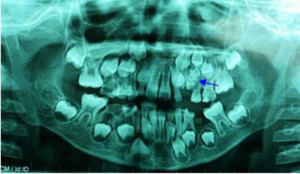

Chiếc răng mọc ngược được lấy từ hốc mũi bệnh nhân.

Các bác sĩ nội soi mũi và nhận thấy có một khối cứng có thể lung lay được, nên đã gắp dị vật ra khỏi mũi. Lúc đó mới phát hiện đó là một chiếc răng thừa, dài khoảng 2cm.

Theo Ths. Bs. Nguyễn Thị Thanh Yến, Khoa Tai-Mũi-Họng, Bệnh viện Quốc tế Hoàn Mỹ, đây là trường hợp hy hữu khi răng mọc ngược trong hốc mũi. Nếu không kịp thời lấy dị vật ra khỏi hốc mũi, người bệnh có nguy cơ hình thành nang xương hàm trên dẫn đến tiêu xương hàm trên không thể hồi phục, ảnh hưởng lớn đến chất lượng cuộc sống.